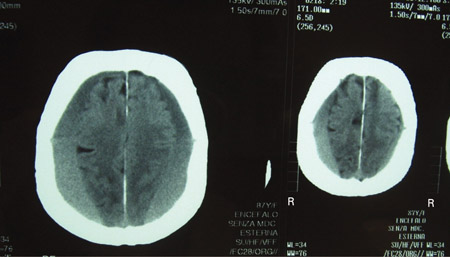

[Figure caption and citation for the preceding image starts]: CT scans of the brain of an 80-year-old man with a gait disorder and a progressive cognitive impairment dating back about 6 months, showing a bilateral chronic subdural haematoma up to the convexityAdapted from BMJ Case Rep. 2009;2009:bcr06.2008.0130 [Citation ends].

The investigation of choice for all patients who have suspected acute or chronic subdural haematoma (SDH) based on the history and the physical and neurological examinations.[48][49][56] Subdural fluid collections are usually crescentic in shape and unlike epidural haematomas which are lenticular, and typically do not cross suture lines.[57] Acute haematomas are hyperdense, isodense, or mixed-density.[33][58][59] Rarely, acute SDHs may be almost isodense relative to the brain parenchyma, for example, in the hyperacute phase in a profoundly anaemic patient or in a patient with an arachnoid tear and a mixture of haemorrhage and cerebrospinal fluid. There may be effacement of the underlying sulci or midline shift, effacement of cisterns or other signs of herniation, or skull fracture or other intracranial haematomas. Cerebral swelling may be manifested as the loss of grey-white matter distinction or gyral integrity. SDHs that have a hypodense 'swirl' inside them signify potential hyperacute haematoma with active bleeding.[60][61]